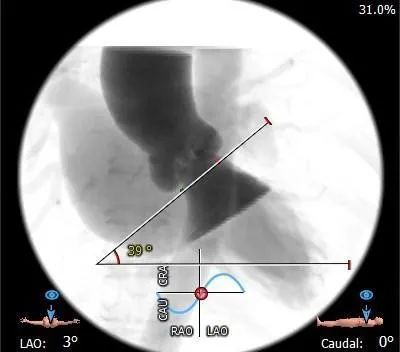

冠脉造影

主动脉根部造影

球囊预扩